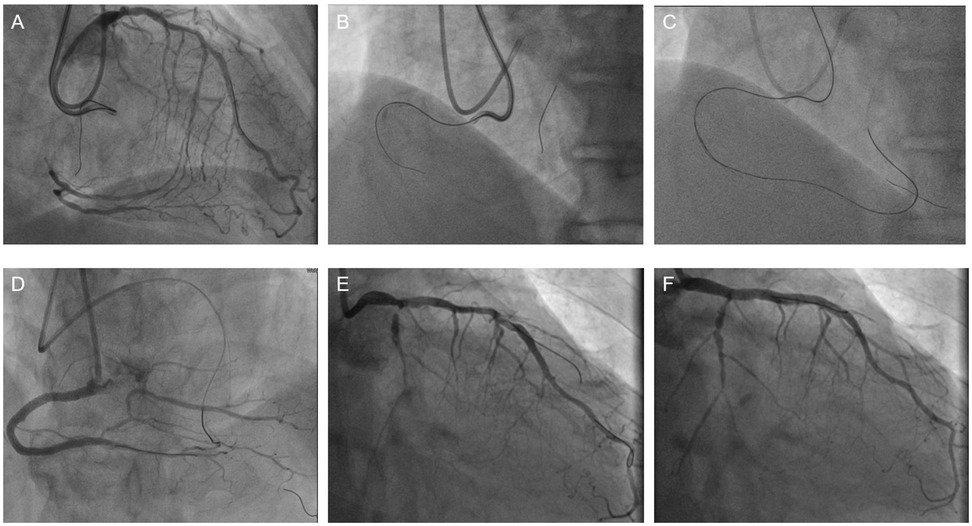

Figure 3

Six-panel angiogram showing coronary arteries. Panels A, D show right coronary artery with visible branches. Panels B, C, E, F depict left coronary artery and its branches from various angles, highlighting different areas of contrast and vessel pathways.

Figure 3. A Bilateral angiography demonstrating total occlusion of the proximal RCA and critical stenosis of the left main coronary artery. (B) Failed anterograde guidewire crossing through the RCA occlusion. (C) Retrograde recanalization achieved via septal collateral channels. (D) Final angiographic result after deployment of four drug-eluting stents in the RCA, with restored TIMI grade 3 flow. (E) CAG indicates severe stenosis of the LCA. (F) The image of successful stent implantation in the LCA.

The surgical procedure: On February 17, 2025, PCI was performed on the patient with the assistance of IABP. First, punctures were made in the right radial artery and brachial artery, and 6F and 7F arterial sheaths were inserted, respectively (Figures 2A,B). Then, an IABP was placed through the left brachial artery (Figure 2C). A guiding catheter 1 was advanced through the right brachial artery sheath to the ostium of the RCA, and another guiding catheter 2 was advanced through the right radial artery sheath to the ostium of the left main trunk for bilateral angiography (Figure 3A), clearly visualizing the course of the distal RCA. Under the support of microcatheter 1, five guide wires (guide wires 1 and 2: SION Blue AHW14R004S, Asahi; guide wire 3: XT-A APW14R009S, Asahi; guide wires 4 and 5: Gaia First AHW14R007P, Asahi) were sequentially used, but none could cross the occluded segment in the mid-RCA (Figure 3B).Under the support of microcatheter 2, guide wire 2 was advanced through the septal branch–posterior descending (PD) collateral in a retrograde manner into the distal segment of the RCA via guiding catheter 2. Subsequently, guide wires 6, 7, 8, and 9 were sequentially advanced through microcatheter 2 to attempt retrograde recanalization. Guide wire 9 successfully traversed the occluded mid-RCA segment and reached the RCA ostium (Figure 3C). Balloon 2 was used to compress the guide wire, and microcatheter 1 was withdrawn. The extension catheter was advanced into the proximal segment of the RCA through guide catheter 1. Microcatheter 2, along with guide wire 9, was advanced into the extension catheter in the RCA. Guide wire 10 was exchanged in reverse through guide catheter 1. Through guide catheter 1, guide wire 11 was inserted into microcatheter 2. Guide wire 11 was then advanced through microcatheter 2 to the distal segment of the RCA, after which microcatheter 2 was withdrawn. Over guide wire 11, the lesion was pre-dilated sequentially with a balloon, and an Intravascular Ultrasound (IVUS) catheter was advanced to the distal segment of the RCA and pulled back to assess the lesion and guide stent placement. Eventually, four drug-coated stents were successfully implanted (Figure 3D). IVUS assessment showed good stent apposition. Repeat angiography revealed no residual stenosis within the stent and no occlusion of major branches. The procedure proceeded smoothly without any intraoperative complications. On February 21st, the patient underwent left coronary artery intervention again. Two drug-coated stents were implanted in the LM-LAD, and Drug-coated balloon (DCB)dilation was performed in the LCX (Figures 3E,F). The wound healed well after the procedure, and the patient was discharged two days later. After 12 weeks of follow-up, the patient reported no discomfort, and blood circulation in both upper limbs was good. The patient's hospitalization timeline is shown in Figure 4.